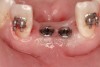

Figure 11  Six months after extraction and augmentation, orthodontic therapy was completed and the patient returned for implant placement. Adequate hard and soft tissues were present.

Figure 11

Figure 12  Flapless, computer-guided implant placement was performed. A transmucosal healing mode was chosen, with the placement of standard healing abutments.

Figure 12

Active tooth movement was complete approximately 6 months after surgery, and a second CBCT scan was taken to evaluate the site prior to implant-placement surgery. With the adequate presence of both hard and soft tissues in the edentulous area (Figure 11), it was determined that no further tissue augmentation was required to place implants in their prosthetically desired positions. At this point, the virtue of not having to deal with the removal of the mesh was apparent. Because regeneration was successful, and surgical re-entry to remove a titanium mesh and fixation screws was unnecessary, a flapless, computer-guided surgery could be considered utilizing software to fabricate the templates (Figure 12). This would reduce morbidity for the patient and enhance implant placement accuracy. Because the procedure was minimally invasive, postoperative bleeding was minimal, making it easier for the orthodontist to replace the arch wire and attached denture teeth for fixed provisionalization postoperatively.